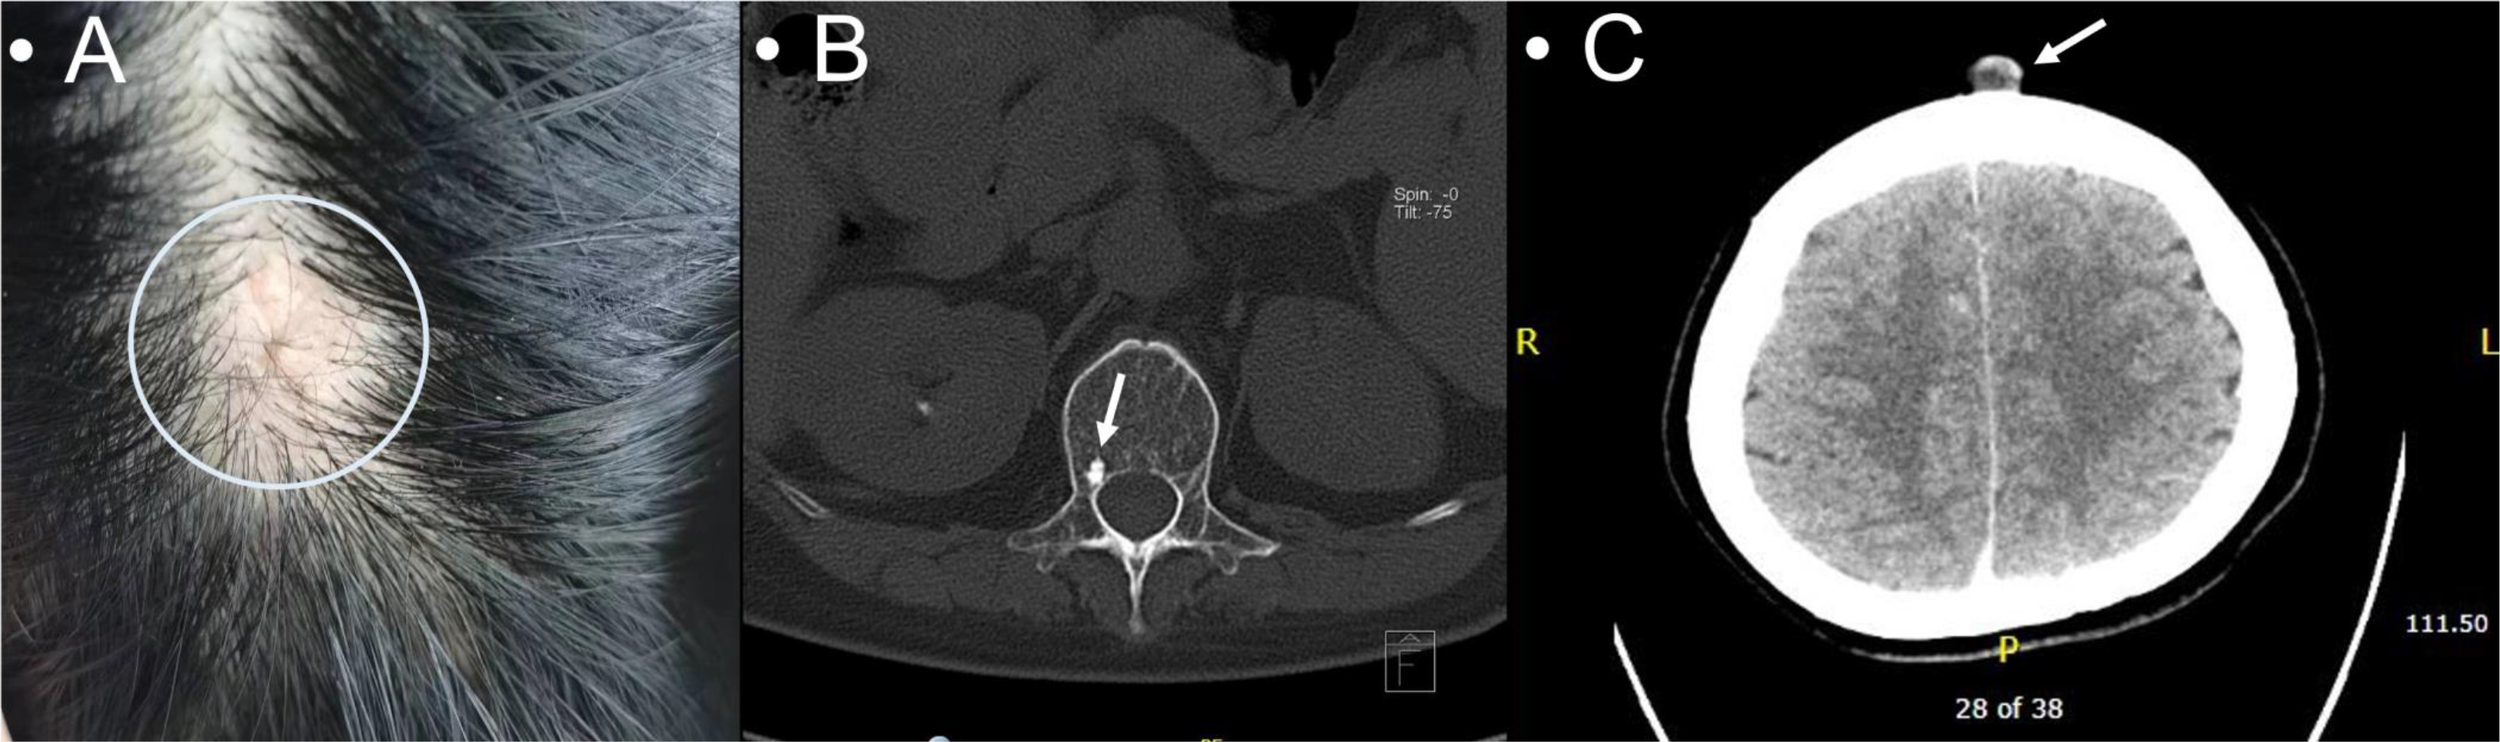

This case involved a 40-year-old Chinese woman with bilateral breast masses and occipital scalp lesions. In July 2020, she underwent evaluation for palpable masses in both breasts presenting with no nipple discharge or skin changes. She reported no other symptoms. Her past surgical history included a partial hip replacement and a left salpingo-oophorectomy. She did not have any pertinent medical or family history. She had no specific risk factors related to breast cancer. Physical examination revealed several lumps: a 2.0 × 2.0-cm firm, non-mobile mass with poorly defined borders in the right breast’s outer lower quadrant; a 3.5 × 2.5-cm mass with similar characteristics in the left upper medial region; a 2.5 × 1.5-cm enlarged node in the right axillary region; no significant enlarged lymph nodes on the left; and a 2.0 × 0.5-cm non-mobile nodule in the occipital scalp region (Figure 3A). A diagnostic mammogram showed multiple nodules with calcifications in both breasts (BI-RADS 4a-b). Breast ultrasound identified several hyper- and hypoechoic masses with calcifications, the largest being 2.7 × 2.5 × 2.7 cm in the right breast (BI-RADS 4c) and 3.7 × 2.0 × 3.9 cm in the left breast (BI-RADS 4b). A full-body CT scan revealed enlarged right axillary lymph nodes, compression fractures in the 12th thoracic spine, and a hyper-dense area in the 1st lumbar spine, suspicious for metastases. She underwent an ultrasound-guided vacuum-assisted excision of the right breast mass. She also had right axillary lymph nodes and occipital scalp nodules (Figures 3B, C). The pathology reports were consistent across all samples indicating invasive mucinous carcinoma with positive hormonal receptors (ER and PR), low Ki-67, and negative ErbB2 (Supplementary Figures 2A–D). She was ultimately diagnosed with right Stage IV (pT3N1M1) breast mucinous carcinoma and left Stage IV (pT2N0M1) breast mucinous carcinoma.

Figure 3

A 2.0 × 0.5-cm non-mobile non-erythematous elevated poorly demarcated nodule in the occipital scalp (A); hyperdensity in the 1st lumbar spine suspicious for metastases (B); a cutaneous occipital scalp nodule on the CT scan (C).